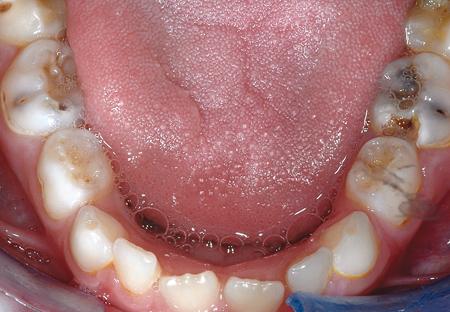

Oral disease

.pull-left[

-

Dental caries The most common chronic disease of children (25%), and adolescents (59%). Bacteria feed on food debris. Bacteria produce acids leading to demineralization and destruction of the teeth.

Periodontal disease Bacteria living in tissues surrounding and supporting the teeth; An over-aggressive immune response can subsequently lead to loosening and finally loss of teeth.

]

.pull-right[

.image-75[